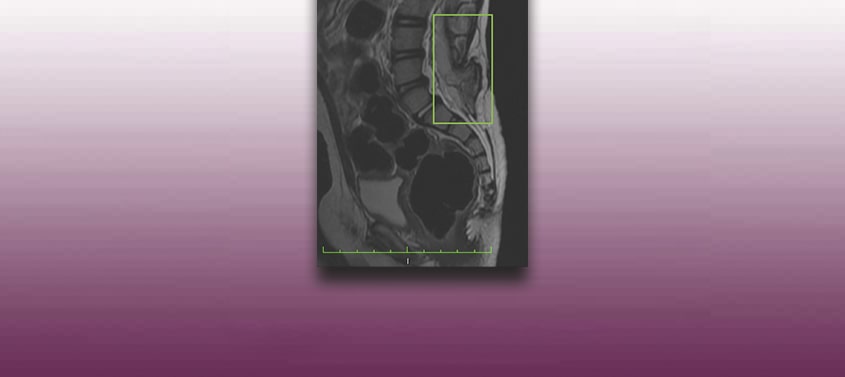

Tethered cord with spina bifida – meningocele or myelomeningocele – or Tethered Cord Syndrome

Last update: 17/06/2020, Dr. Miguel B. Royo Salvador, Medical Board number 10389. Neurosurgeon y Neurologist. Definition In normal conditions, the spinal cord is held within the spinal canal only by the denticulate ligaments and the filum terminale, a ligament that connects the conus medullaris to the first coccygeal vertebrae. When the mobility of the […]